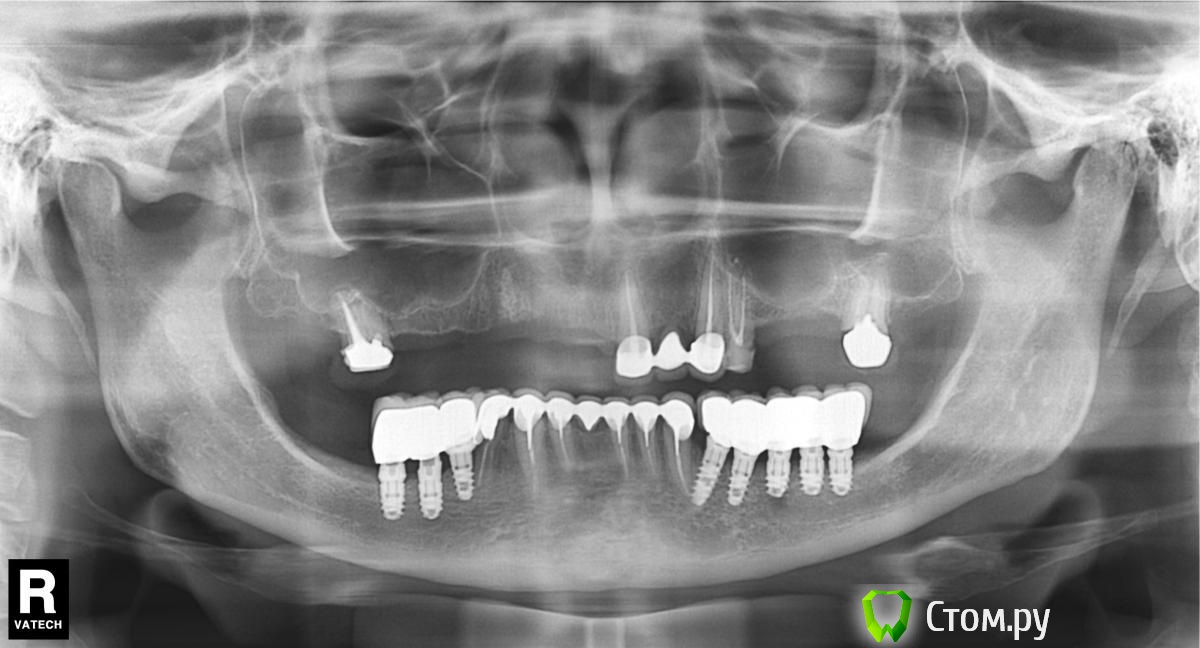

biv29 Опубликовано 30 апреля, 2014 Поделиться Опубликовано 30 апреля, 2014 (изменено) Уважаемые коллеги, прошу вашей помощи в составлении плана комплексной реабилитации пациентки.Пациентка 1962 г.р., 2 года назад были установлены имплантанты на н/ч, осуществлено протезирование (работал другой стоматолог-ортопед). Имеется вертикальная резорбция кости н/ч, рецессия десны, оголение имплантантов.На в/ч сохранены 17, 21, 23, 24, 27. Установлен ЧСПП. 21-23 МК-мостовидный протез (коронка 23 не доходит до десневого края). 24 - временная пластмассовая коронка.Имеется снижение высоты прикуса.- Я склоняюсь к следующему варианту работы:удаление 17, 21, 23, 24, 27; проведение синус-лифтингов с двух сторон, аугментация, установка имплантантов; временное протезирование на время реабилитации после операции, временное протезирование на пластмассовых коронках, постоянное протезирование МК.1. При этом плане возникает вопрос о временном протезировании сразу после хирургического вмешательства. Имплантолог против установки ПСПП на в/ч. Как поступить в этом случае? Использовать ли стабилизацию ПСПП и его фиксацию на мини-имплантантах? Достаточно ли будет мягкой подкладки на внутренней поверхности ПСПП?2. Считаете ли целесообразным осуществить протезирование сначала на в/ч без переделки орт. конструкций на н/ч? 3. 21, 23, 24 - стоит удалять или есть вероятность, что еще послужат? 4. Какой план протезирования вы бы предложили в данной клинической ситуации? Заранее спасибо за возможные ответы. Изменено 30 апреля, 2014 пользователем biv29 Ссылка на комментарий